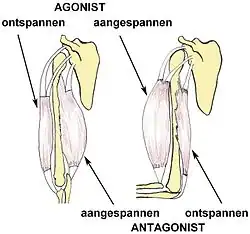

| Muscle imbalance is an imbalance between agonist and antagonist muscles. |

Muscle balance is necessary for muscles to perform their customary roles and move normally; muscle imbalance occurs when there is a lack of parity between corresponding agonist and antagonist muscles.[1] Muscular imbalance can also arise when a muscle performs outside of its normal physiological muscle function.[2][3]

Muscles are considered balanced when the muscles that surround a joint work together harmoniously, i.e. with appropriate opposing force, to keep the bones aligned where they meet at the joint. This permits normal human movement.[3]

Functional Imbalances are when the muscles adapt in response for detailed muscle movement patterns, including unequal values in strength or flexibility of antagonistic muscle groups, usually apparent in athletes of different sports ranging from soccer to baseball.[1] This type of imbalance is the first stage, it is painless, atraumatic (causes minimal tissue injury[9]), adaptive to change and activity specific.[1] Studies confirm this as they find the link between muscle imbalance and athletes who perform at elite levels, this also relates to injury occurrence is not treated to muscle specific rehabilitation.[10]

Pathological muscle imbalance occurs when the imbalance of the muscles begin to inhibit function.[1] This pathological muscle imbalance may or may not result from a traumatic event, it is usually associated with pain and dysfunction, although there are cases where pain is not apparent, however pathological muscle imbalances ultimately lead to joint dysfunction and changes in normative muscle movement patterns.[1] It would be good to note that this imbalance can progress to either tissue damage and pain or altered movement pattern, with the constant being tightness or weakness.[1] A study has shown that athletes that exhibit shoulder pain have been linked to have decreased rotator cuff muscle strength and have concluded that they are more susceptible to rotator cuff tears and type II superior labrum anterior and posterior lesions.[11]